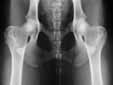

| Zugelassene

Röntgenstelle für HD

(Hüftgelenksdysplasie), ED

(Ellenbogengelenksdysplaie) und OCD

(Osteochondrosis dissecans). |